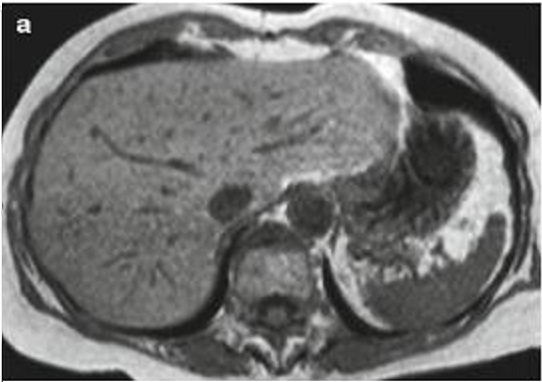

Image IRM de steatose fu foie

: Image de

hyperintense sur T1 et hypointense surT2 . L'infiltration graisseuse du foie provoque une diminution de

l'attenuation du parenchyme du foie . Sur le foie normale le

signal du parenchyme hepatique est similaire sur toutes les

images "in phase " et "opposed phase " . Dans steatose du

foie le signal du foie est hyperintense relative avec la rate (

T1 in phase ) et a opposed-phase , par la chute de

signal , image du foie est hypointensite ,

Image ỈRM normale du foie en

T1 coupe axiale .Image du foie est

hyperintense que la rate |

|

T2 coupe axiale . Le parenchyme du foie est moins intense que

la rate . |

Steatose du foie : en phase .

Image IRM du foie |

Steatose du foie : Op de phase . |